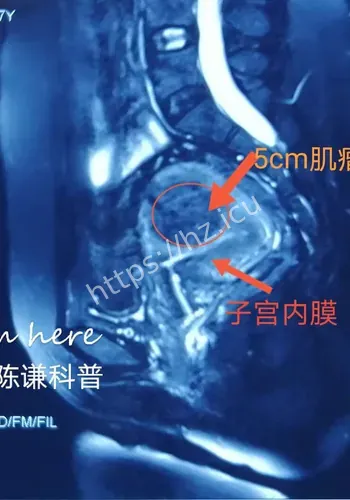

对观众来说,这类热点的影响,往往体现在它会不会改变自己对22厘米肌瘤致孕妇子的判断,或者会不会影响后续生活中的选择与讨论。检查揭示出一连串环环相扣的罕见致命危机:一个大小约为13.212.822.4厘米的巨大肌瘤,上缘顶至剑突,左右分别霸占整个腹腔,甚至超出超声探头的单一切面探测范围,并且提示血运丰富。因肌瘤推挤,子宫发生罕见的“箝闭”,即子宫体向后倾倒、死死卡在直肠窝内,宫底位置低于宫颈外口,整个子宫呈“倒置”状态。